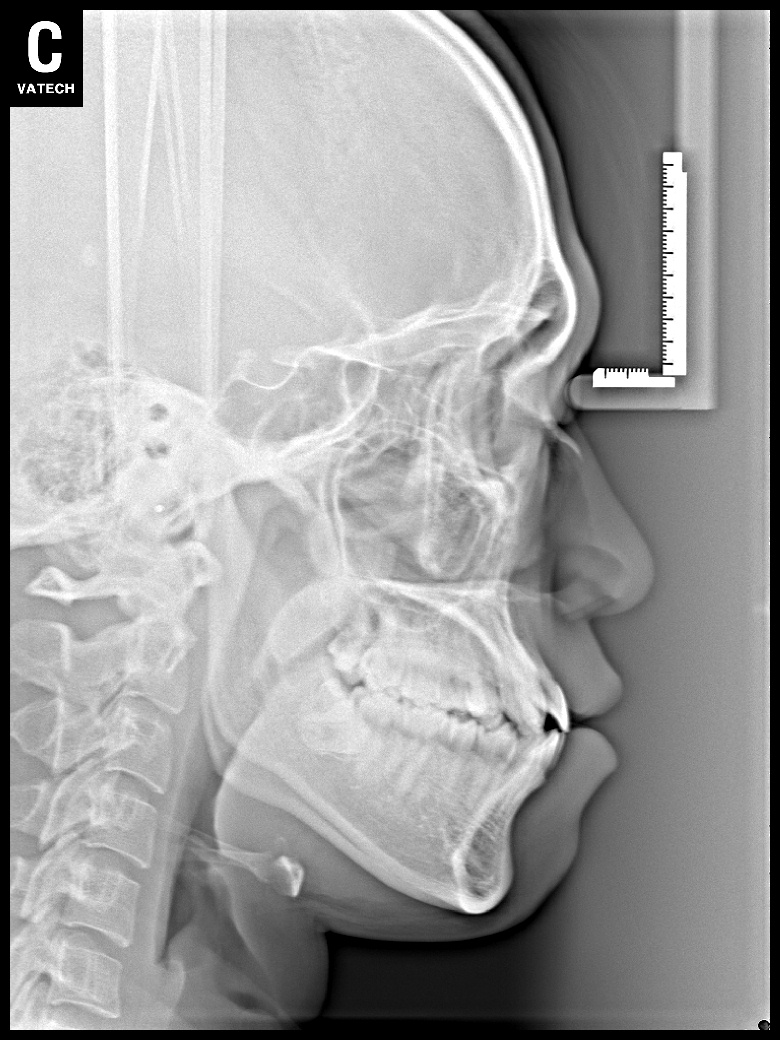

치료 전 사진입니다.